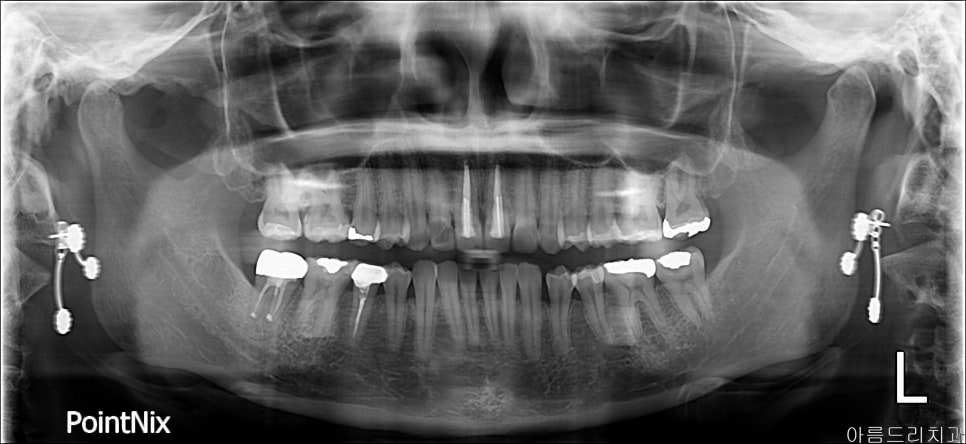

치아를 뽑았다가 그 자리에 다시 심는 치아 재식술

치아 재식술이 뭔가요? 치아를 뽑아서, 눈으로 염증 부위를 직접 확인 후 처치하여 뽑은 부위에 다시 재식립하는 시술을 말합니다.

재식 _ 전

얼마 전 조00이라는 환자분이 신경치료를 모두 마친 후 금으로 크라운까지 세팅된 치아에 통증을 호소하시면서 내원하셨습니다. 아직 나이도 어리고, x-ray나 CT로 염증을 확인하기 어려웠습니다.

이러한 경우 발치하고 임플란트를 해야 하나요?라고 질문하시더군요. 발치하기 전 치아를 살릴 수 있는 재식술에 대해 설명 들으시고 당일 바로 진행되었습니다.